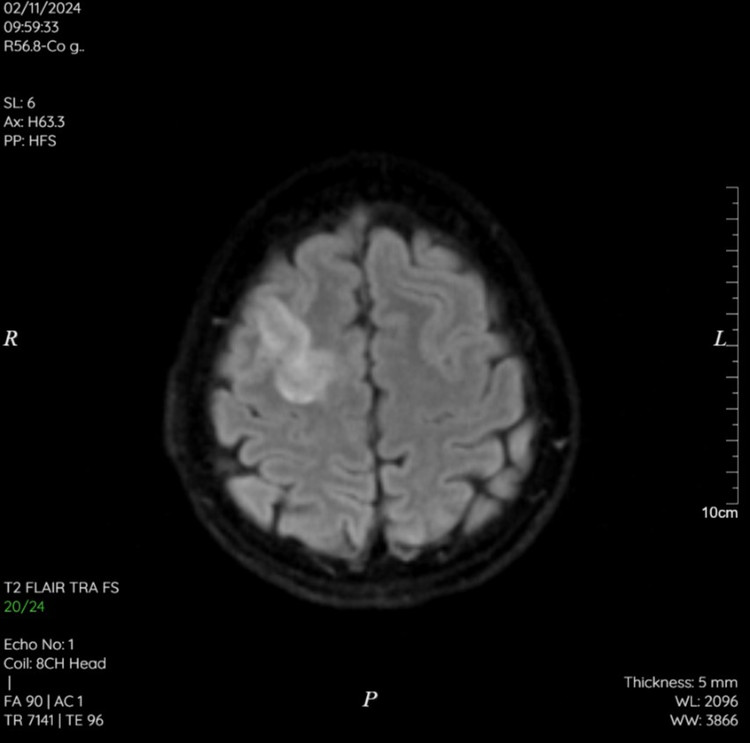

Qua thăm khám lâm sàng và cận lâm sàng bước đầu, bệnh nhân được chẩn đoán Huyết khối tĩnh mạch vỏ não vùng đỉnh 2 bên và phần trước xoang dọc trên - Nhồi máu vỏ não đỉnh phải.

| Kết quả chụp CT bệnh nhân được chẩn đoán Huyết khối tĩnh mạch vỏ não vùng đỉnh 2 bên và phần trước xoang dọc trên. Ảnh BVCC |